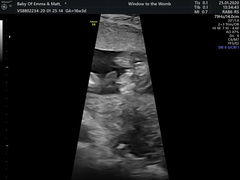

I'm 16+3 and went today privately to have my gender scan. I've had put in my head since day one that we'll be having a boy, today at the scan we got told we'd be having a little girl. We're very much in shock because all we've been convinced by people is it's a girl 🤣. We're happy and we didn't mind the gender as long as they were heathy. The only thing that's on my mind was that it took a while for the sonographer to figure out the gender and I had to cough a few times to get her to budge! Me and oh could have sworn we saw a little penis in the photos but the sonographer saw the three lines for a burger for a girl. I've attached the scans and the photos we thought were a boy. Is it the placenta that we saw? I feel awlful questioning it and we are happy but would be happy to hear your thoughts!